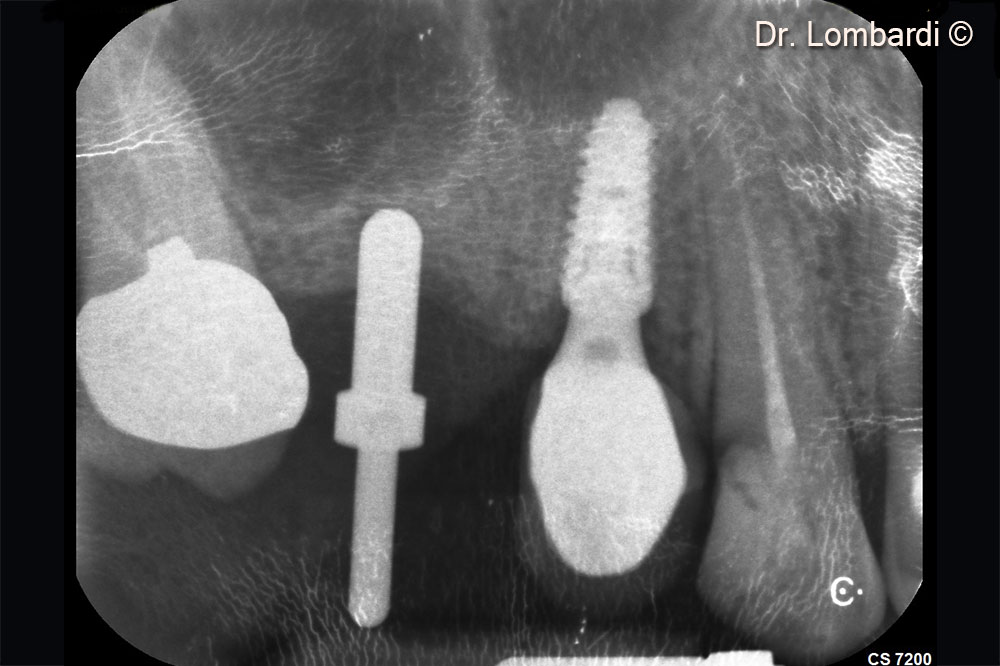

Putty gently detaches and displaces the sinus membrane

Immediate implant insertion is required to counteract the physiological biomaterial shrinkage